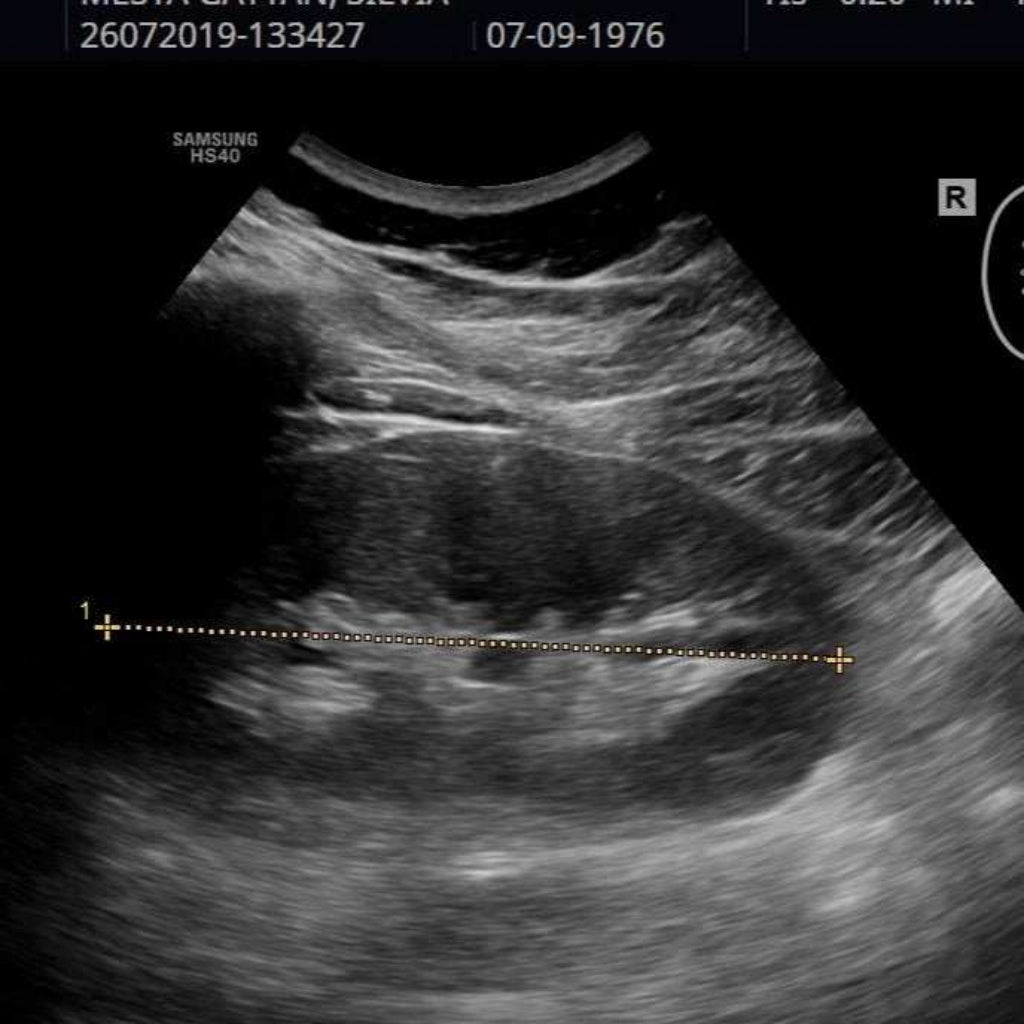

El ultrasonido renal es una herramienta de diagnóstico versátil y ampliamente utilizada en el campo de la medicina para evaluar la salud y función de los riñones y las vías urinarias, así como para diagnosticar y monitorear una variedad de condiciones relacionadas con el sistema urinario.